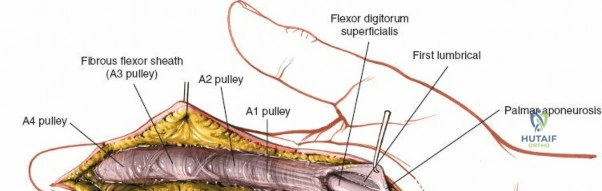

Within the fibro-osseous tunnel, these tendons are enveloped by a synovial sheath that facilitates smooth gliding and nutrition. The integrity of the pulley system, composed of annular (A) and cruciate (C) ligaments, is critical for preventing tendon bowstringing and maintaining efficient mechanical advantage. Typically, five annular pulleys (A1-A5) and three cruciate pulleys (C1-C3) are described in each finger. The A1 pulley is at the metacarpophalangeal (MCP) joint level, A2 at the proximal phalanx, A3 at the proximal interphalangeal (PIP) joint, A4 at the middle phalanx, and A5 at the distal interphalangeal (DIP) joint. The A2 and A4 pulleys are considered the most critical for preventing significant bowstringing.

Once the subcutaneous tissue and neurovascular bundles are retracted, the fibrous flexor sheath is visible. This appears as a glistening white, tough structure enveloping the flexor tendons.

The sheath is incised longitudinally. The specific pulleys that need to be released depend on the pathology and zone of injury.

- A1 Pulley Release: For distal palmar or MCP joint access (e.g., trigger finger release, A1 pulley excision for tumor). The A1 pulley can be completely incised longitudinally from proximal to distal without significant risk of bowstringing, as the A2 pulley is the primary stabilizer at the proximal phalanx base.

- Digital Pulleys (A2-A5, C1-C3):

- For flexor tendon repair, typically the A2 and A4 pulleys must be preserved to prevent bowstringing, which significantly impairs mechanical efficiency.

- The A1, A3, and A5 pulleys, and the cruciate pulleys (C1, C2, C3), can be incised longitudinally or partially vented to expose the tendons and allow for repair.

- When accessing Zone II (no-man's land), the incision usually involves opening the A1, A3, and C1/C2/C3 pulleys, carefully preserving the A2 and A4 pulleys.